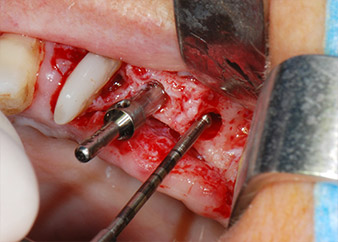

En primer lugar, en un intento por gestionar el problema endo-periodontal, el resto de la superficie radicular se desbridó con cuidado con un equipo piezoeléctrico (Piezomed de W&H, utilizado con el inserto S1 con forma de espátula, concebido en un principio para la erosión de la pared lateral del seno) (figura 4). A continuación, el ápice se erosionó con el mismo instrumento para eliminar el tejido apical infectado residual y reducir las posibles ramificaciones accesorias del canal radicular (apicectomía) (figura 5). No fue necesario realizar un retrorellleno, puesto que la obturación ortógrada se acababa de revisar.

Antes de colocar el implante, el tejido infectado del hueso alveolar ubicado en el lugar del implante y alrededor de los dientes del pilar se retiró con un inserto concebido en un principio para modelar huesos y recoger virutas óseas: Piezomed y el inserto B5 (figuras 6 y 7).

En el siguiente paso, los lechos del implante se prepararon en las posiciones 25 y 26 con instrumentos rotatorios, utilizando un contra-ángulo con un coeficiente de transmisión de 20:1 (WS-75 L, W&H), junto con el nuevo potente motor de implantes Implantmed de W&H (figuras 8 y 19).

La preparación final junto al seno se realizó de nuevo con un inserto piezoeléctrico (Piezomed S2).